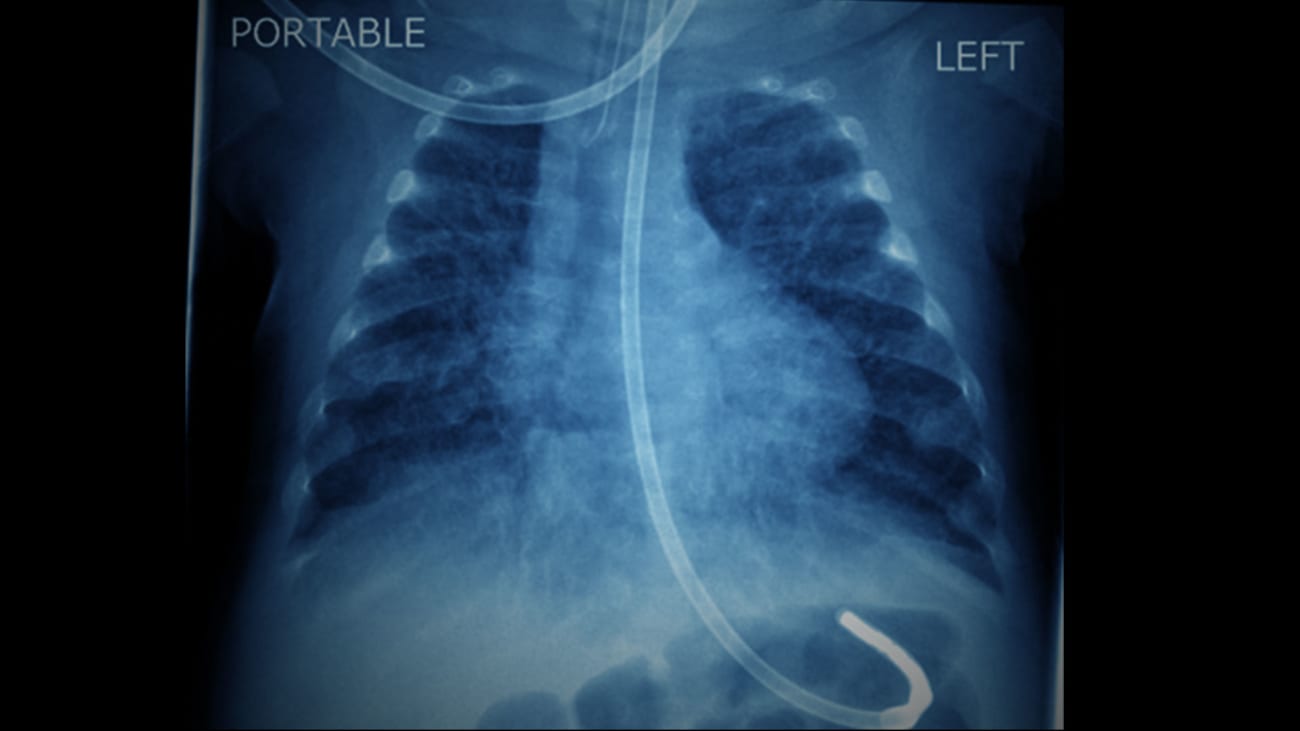

The multidisciplinary Chronic Lung Care Program at Mount Sinai Kravis Children’s Hospital was established to help care for infants in the NICU with evolving and established chronic respiratory failure.